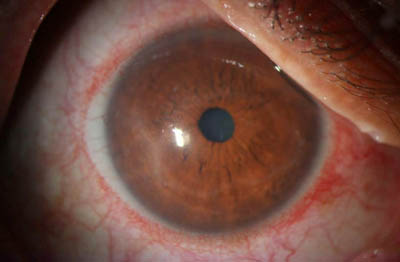

- Superficie corneal irregular y grisacea

- Opacidades granulares en parche

- Formación de lineas epiteliales elevadas de aspecto granular, que pueden dar imágen de seudodendritas

- Opacidades superficiales satélites

- Ulceración epitelial variante

- Formación de anillo inmunológico

Superficie corneal irregular y grisácea

Opacidades granulares en parche

Opacidades superficiales satélites

Ulceración epitelial variante

Anillo inmunológico de Wessely

- Es la expresión de la interacción de los antígenos extraños con los anticuerpos que se difunden desde los vasos limbares hacia el estroma.

- Representa la formación de un complejo inmune que activa el sistema del complemento.

- El anillo de Wessely contiene principalmente neutrófilos